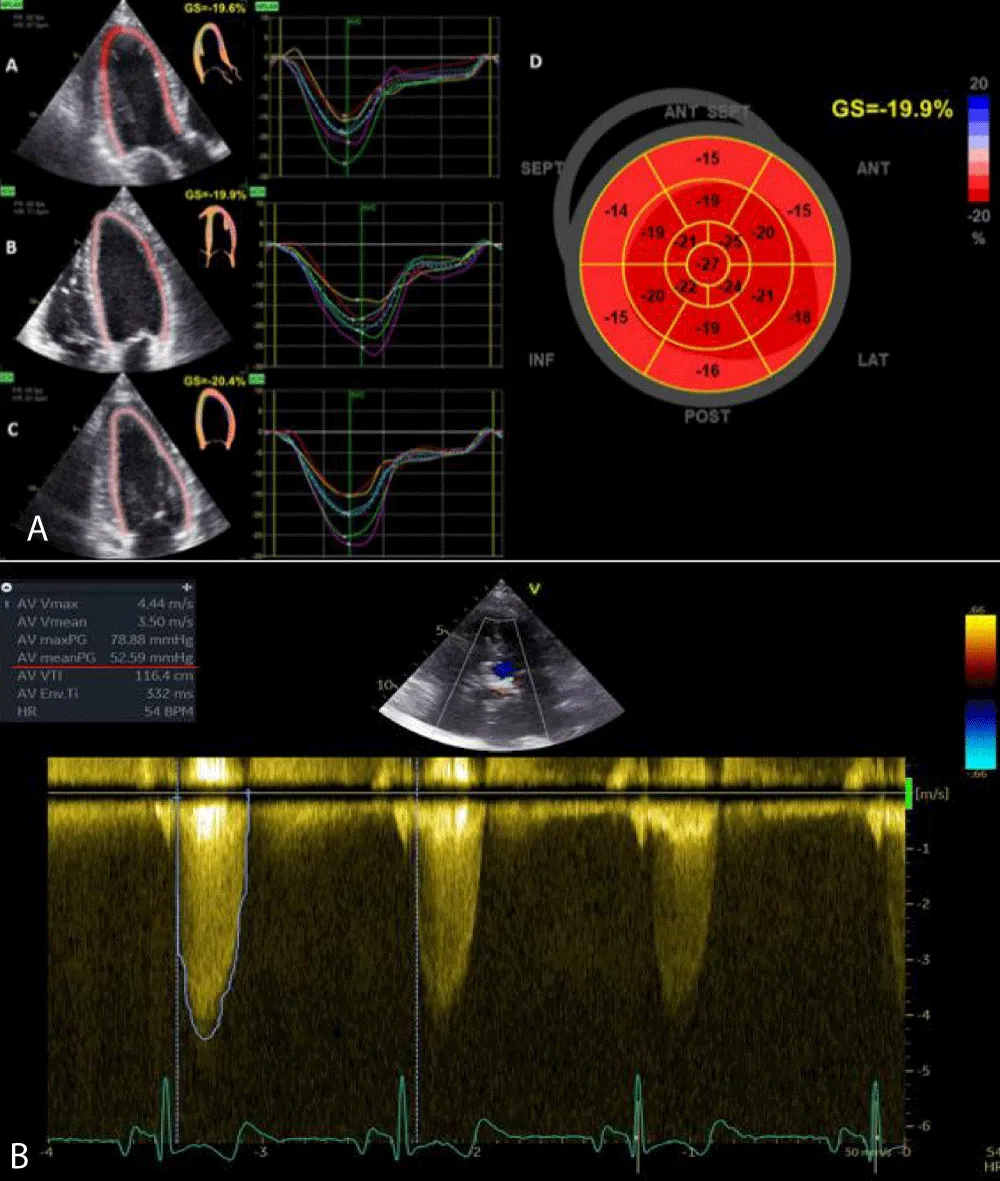

GLS was calculated offline with images obtained from apical windows 4, 3, and 2 chambers. The software automatically calculated the degree of longitudinal deformation. The myocardial was divided into six zones (inferior, infero-septal, antero-septal, anterior, antero-lateral, infero-lateral). The average strain profile of the wall was analyzed for each area. From this analysis, we obtained the systolic peak of longitudinal strain (PSLS: Peak Systolic Longitudinal Strain) which is the maximum negative value of deformation during the ejection phase. The GLS was calculated from the averages of the values obtained by the individual myocardial walls for each window (Figure 1). 2D imaging was used for the calculation of the LVM. The formula for determining the mass was LVM = Area x Height. The area was calculated from the parasternal short-axis window (at the level of the papillary muscles) by subtracting the ventricular cavity from the area calculated at the epicardium level. The height was measured from the 4-chamber window as a base-apex distance. The ventricular mass was also indexed according to the formula LVMi = LVM/BSA. According to the guidelines, the upper reference value was 88 g/m2 in women and 102 g/m2 in men.

Download Image

Figure 1: Bull-eyes of 17 segments, calculating GLS (A) and CW doppler through the aortic valve, which shows severe aortic stenosis (B).